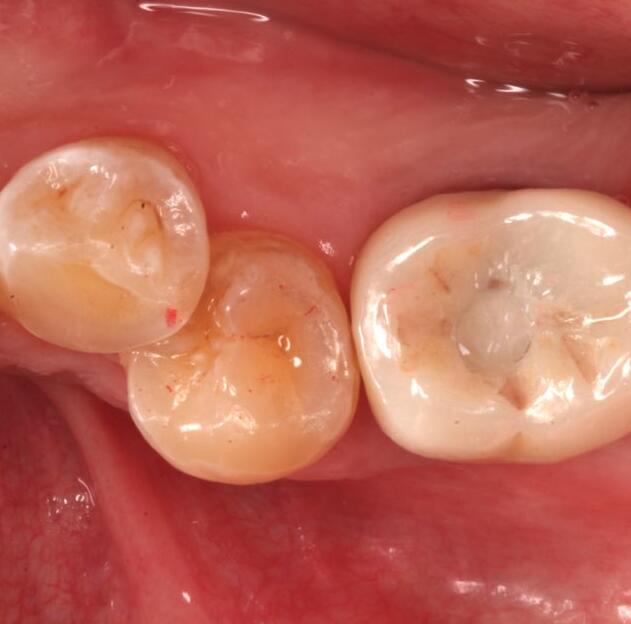

活動(dòng)義齒是一種可自行摘帶的牙齒修復(fù)的方法,選擇活動(dòng)義齒來(lái)恢復(fù)牙齒的使用狀態(tài),是因?yàn)檫@種調(diào)節(jié)方式對(duì)我的口腔損傷比較小。在做完手術(shù)后,不會(huì)感覺我的牙齒有不舒適的情況,而且平時(shí)自己就有戴假牙的習(xí)慣,所以做活動(dòng)義齒反而會(huì)覺得更方便,更適應(yīng)一些。在做活動(dòng)義齒的調(diào)節(jié)時(shí),我對(duì)活動(dòng)義齒的材料沒有過(guò)敏反應(yīng),并且因?yàn)槔钚γ丰t(yī)生的牙齒修復(fù)調(diào)節(jié)的手法嫻熟,我在做了牙齒的調(diào)節(jié)后,沒有出現(xiàn)其他不良的情況。

牙齒種植是指在牙槽骨內(nèi)植入人工牙根,待人工牙根成活之后,就能夠在其上連接入基臺(tái)和義齒。能夠仿真牙的果,并且其療也是理想的,因此很多人都稱他為人類的第3副牙齒 。種植牙的維持時(shí)間一般在10-20年左右,果好。